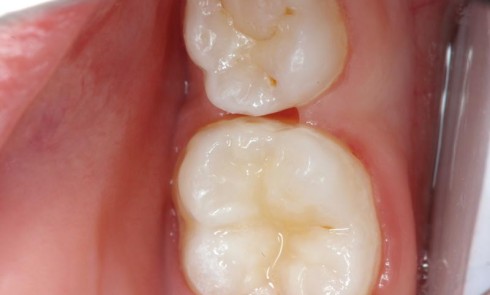

Article réservé à nos abonnés Comprendre les bases de la cariologie en 10 points (partie II)

Agents chimiques agissant sur la balance carieuseUn certain nombre d’agents chimiques peuvent influencer la balance carieuse en agissant sur le...